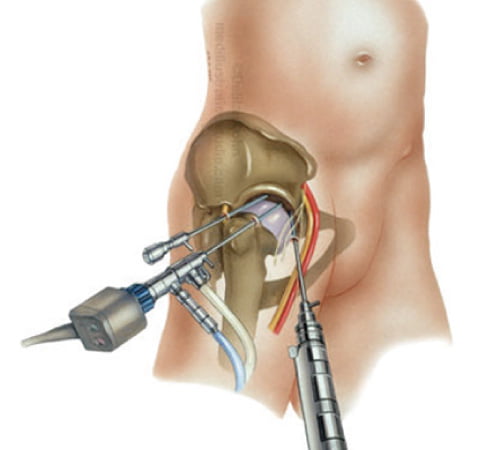

Há pelo menos 30 anos, a videoartroscopia tem se estabelecido como uma poderosa arma no arsenal do cirurgião ortopedista. A artroscopia é uma técnica para cirurgia minimamente invasiva. Através dela, o cirurgião não precisa ver a articulação diretamente com seus olhos. Ele utiliza pequenos orifícios na pele, por onde insere um dispositivo de fibra óptica (artroscópio) conectado a um equipamento de vídeo de alta resolução, através do qual o cirurgião pode acessar as diferentes partes da articulação e inserir instrumentos para manipular e tratar os tecidos lesados.